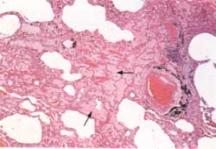

其他輔助檢查:肺功能的異常和嚴重程度與疾病的階段有關,典型者為中、重度的限制性通氣功能障礙、DLCO的下降。肺泡-動脈氧的梯度的升高,如果伴有哮喘則有阻塞性的改變。X線表現與胸膜相對的周圍漸進的密度增強的浸潤影,邊緣不清,呈非節段性、亞段和葉的分布,多位於肺外周2/3,而肺門處較透明,故稱為“肺水腫反轉形狀”,陰影易在原處復發。潑尼松治療後陰影很快吸收。與Loffler’綜合徵相反,CEP的肺浸潤為非遷移性,很少有胸腔積液。不典型的X線表現包括結節狀浸潤、瀰漫性毛玻璃樣的肺泡填充征。胸部CT檢查對於臨床懷疑而X線表現不典型的病例可作CT檢查,CT的表現,在症狀發作的前幾周,大部分表現為典型的密度區、周圍局部的肺泡實變,當症狀持續2個月以上,可見有條索帶狀不透光區,並見縱隔淋巴結腫大。